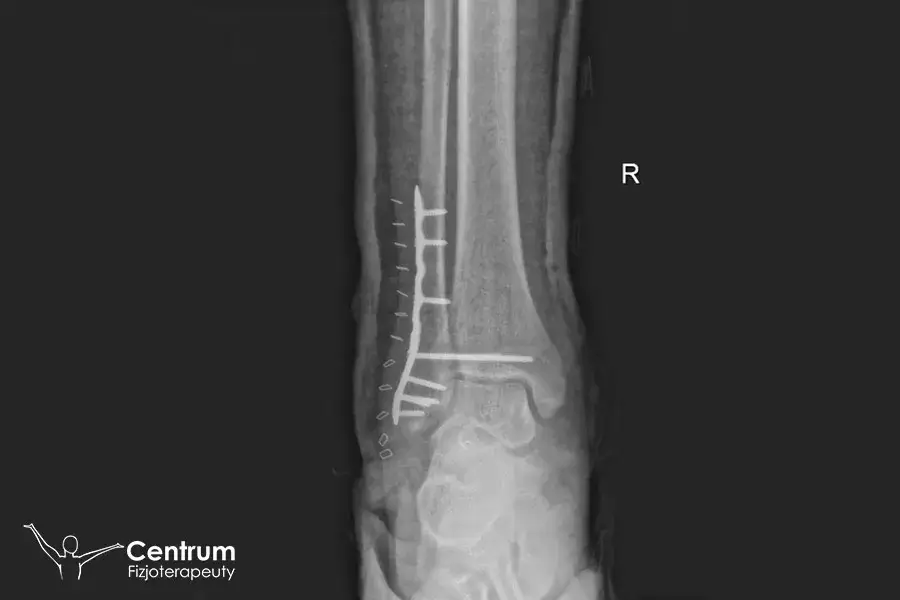

- Metoda leczenia: Leczenie zachowawcze (unieruchomienie w gipsie lub ortezie) jest zazwyczaj krótsze i mniej obciążające niż leczenie operacyjne, które wiąże się z koniecznością zespolenia kości śrubami i płytkami. Operacja, choć niezbędna w wielu przypadkach, może wydłużyć początkowy czas rekonwalescencji.

Leczenie operacyjne jest zazwyczaj konieczne w przypadku niestabilnych złamań, gdzie odłamy kostne są przemieszczone i nie mogą zrosnąć się prawidłowo bez interwencji. Dotyczy to również złamań wieloodłamowych, dwukostkowych (obejmujących kostkę boczną i przyśrodkową) lub trójkostkowych (dodatkowo z uszkodzeniem tylnej krawędzi piszczeli). W takich sytuacjach chirurg zespoluje kości za pomocą śrub, płytek lub drutów, aby zapewnić stabilność i prawidłowy zrost.

Jak wygląda rehabilitacja po operacyjnym zespoleniu kości (płytki i śruby)?

Rehabilitacja po operacji ma wiele podobieństw do leczenia zachowawczego, ale z kilkoma kluczowymi różnicami. Początkowy okres pooperacyjny charakteryzuje się koniecznością ochrony miejsca operowanego i często późniejszym rozpoczęciem obciążania kończyny. Musimy dać czas tkankom na zagojenie się. Następnie, pod okiem fizjoterapeuty, stopniowo wprowadzamy ćwiczenia mobilizacyjne i wzmacniające, zwracając szczególną uwagę na bliznę pooperacyjną i ewentualne zrosty. Indywidualny plan rehabilitacji jest tutaj jeszcze bardziej kluczowy.

Czy czas powrotu do zdrowia po operacji jest dłuższy?

Tak, w wielu przypadkach czas powrotu do zdrowia po operacji może być dłuższy, zwłaszcza w początkowej fazie. Wynika to z konieczności zagojenia się tkanek miękkich po zabiegu oraz często z większej rozległości samego urazu. Jednak ogólne etapy rehabilitacji są podobne, choć często bardziej intensywne i wymagają większej precyzji w doborze ćwiczeń. Ważne jest, aby nie zniechęcać się dłuższym czasem rekonwalescencji, a skupić na systematycznej pracy.